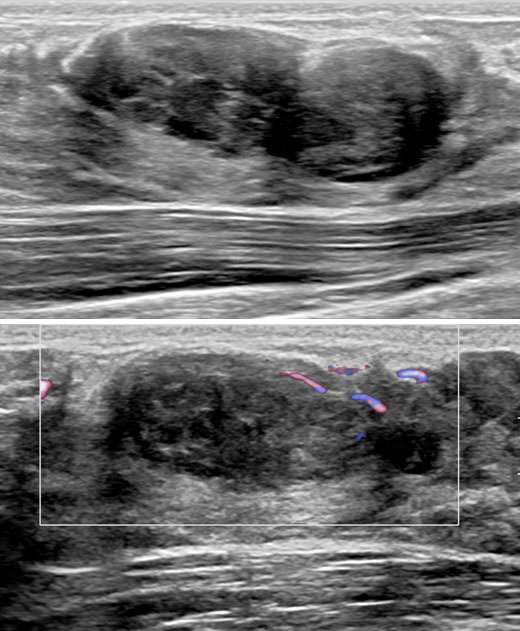

The patient underwent a diagnostic mammogram which revealed extremely dense breasts and an oval mass with circumscribed and obscured margins seen in the right breast at 9 o’clock at anterior depth (Figure 1). Targeted sonographic images were subsequently obtained which revealed a hypoechoic vascular oval mass with circumscribed margins measuring 24 x 10 x 34 mm seen in the right breast at 9 o'clock located 3 centimeters from the nipple (Figure 2). Given the patient’s medical history these findings were given BIRADS-4A and an ultrasound biopsy was recommended.

Case Female Transgender Figure 2

Figure 2: A radial and radial ultrasound images of the area of palpable concern demonstrate a hypoechoic vascular oval mass with circumscribed margins measuring 24 x 10 x 34 mm at 9 o'clock located 3 centimeters from the nipple.